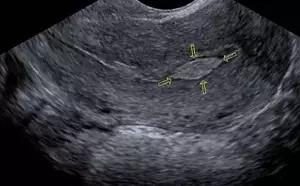

我们能借助的就是B超,绝大多数1cm以上的息肉是可以被阴超发现的,有时候几毫米的也行。B超便宜无辐射,临床应用最多。当然也可以运用CT和MRI来判断,就是贵了点。

B超所见的内膜息肉(箭头所指)